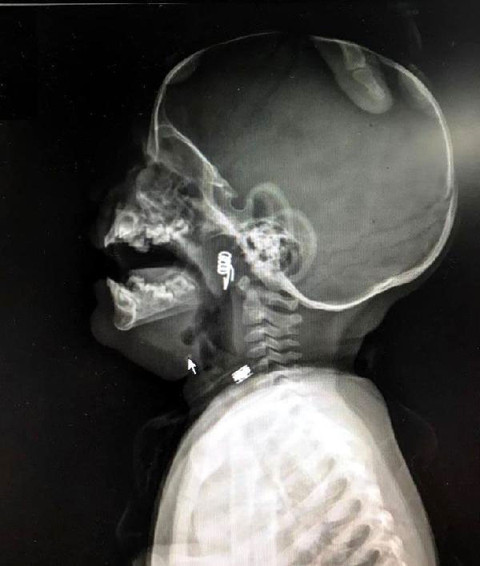

1 yaşındaki bebeğin yuttuğu şeye inanamayacaksınız filmde göründü...

Galerinin tamamı için tıklayınızNevşehir'de 1 yaşındaki erkek bebek Ö.Y., dün akşam saatlerinde elinde mandalla oynarken, parçalanan mandalın yayını ağzına aldı. Duruma müdahale eden bebeğin babası, yayı çocuğunun ağzından çıkarmaya çalışırken, yay bebeğin genzine kaçarak saplandı.